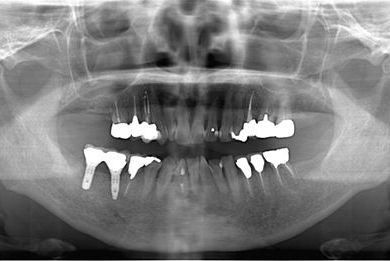

抜歯即日スピードインプラント+セラミック治療

| 治療方針 | 抜歯と土井jにインプラントを埋入し、治療期間を短縮する。 | ||||||||||||||||||||||||||||||||

| 治療内容 | インプラント2本(抜歯即日スピードインプラント)、ハイブリッドセラミッククラウン5本(セラミック用土台2本)、ハイブリッドセラミックインレー1本 | ||||||||||||||||||||||||||||||||

| 治療期間 | 1年3ヶ月 |